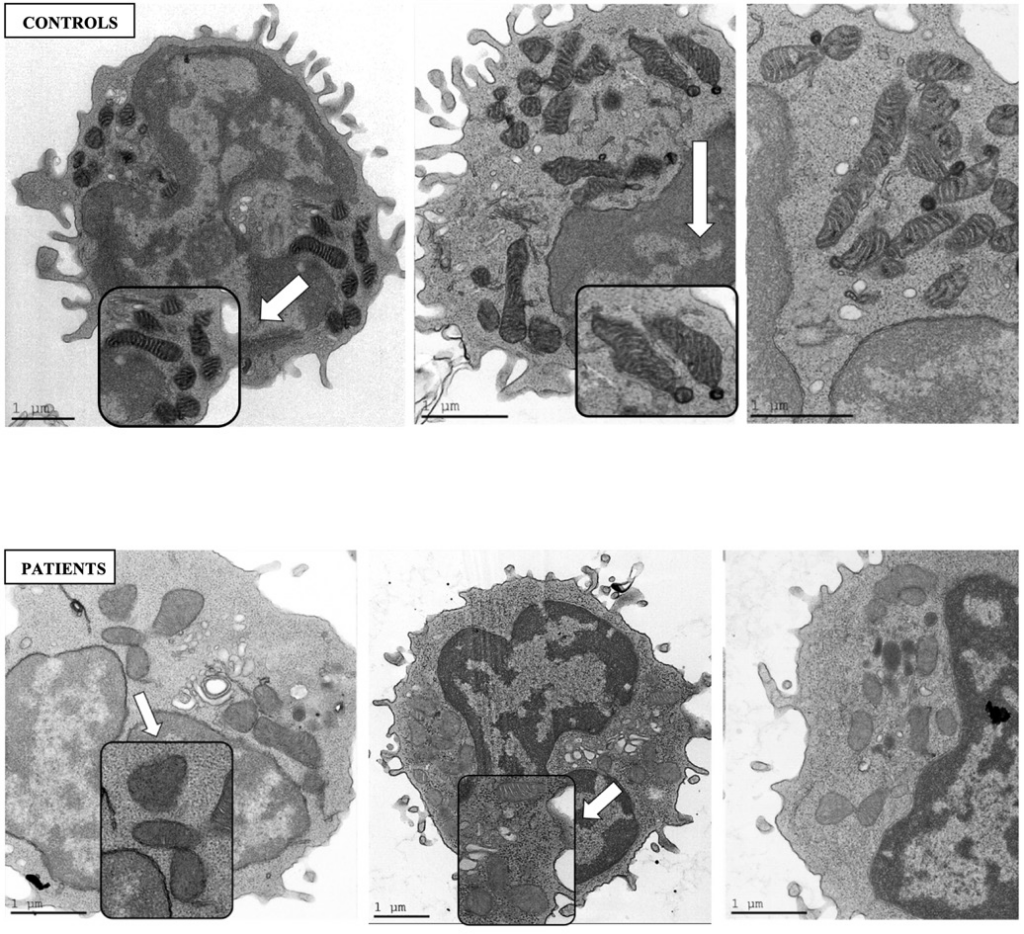

A mitokondriális diszfunkciókkal foglalkozó tanulmányok közül kiemelném még a Clinical and Experimental Rheumatology egyik 2024-es számában megjelent tanulmányt. Ez a tanulmány volt az egyik első, amely közvetlenül vizsgálta a mitokondriumok szerkezetét fibromyalgia betegekben.

A kutatók fibromyalgia betegek perifériás vérsejtjeiből (általában limfocitákból vagy monocitákból) vettek mintát, a sejteket transzmissziós elektronmikroszkóppal (TEM) vizsgálták és összehasonlították az eredményeket egészséges kontrollokkal.

A fibromyalgia betegek mitokondriumaiban a következő eltéréseket találták:

1. Duzzadt mitokondriumok

A mitokondriumok mérete megnőtt, ami gyakran stresszre vagy károsodásra utal. Ez a duzzadás a membránpotenciál csökkenésével járhat.

2. Rendezetlen vagy sérült kristaszerkezet.

A kristák (a belső membrán redői) szétesettek, töredezettek vagy hiányosak voltak. A kristák állapota kulcsfontosságú, mert itt zajlik az ATP-termelés, ami a sejtek energiaellátásáért felelős.

3. Membránkárosodás

A külső vagy belső membrán megvastagodott, hullámos vagy részben sérült volt. (A membrán integritása alapvető a mitokondrium működéséhez.)

4. Megnövekedett oxidatív stressz jelei

Bár ez nem közvetlenül a szerkezet része, a kutatók reaktív oxigén gyökök (ROS) emelkedett szintjét is kimutatták. A ROS károsíthatja a mitokondriumokat, ami tovább fokozza a funkcióvesztést.

Kép forrása: Mitochondrial structural alterations in fibromyalgia: a pilot electron microscopy study (L. Israel1, V. Furer2, S. Levin-Zaidman3, N. Dezorella3, O. Brontvein3, J.N. Ablin2, A. Gross1)